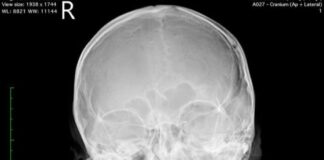

Korban Penganiayaan di Apartemen Formosa Alami Retak di Tengkorak Kepala

AlurNews.com - Rudi (34) warga Kabupaten Karimun yang menjadi korban penganiayaan di tempat hiburan malam (THM) yang berada di lantai 7 Apartemen Formosa, Nagoya,...